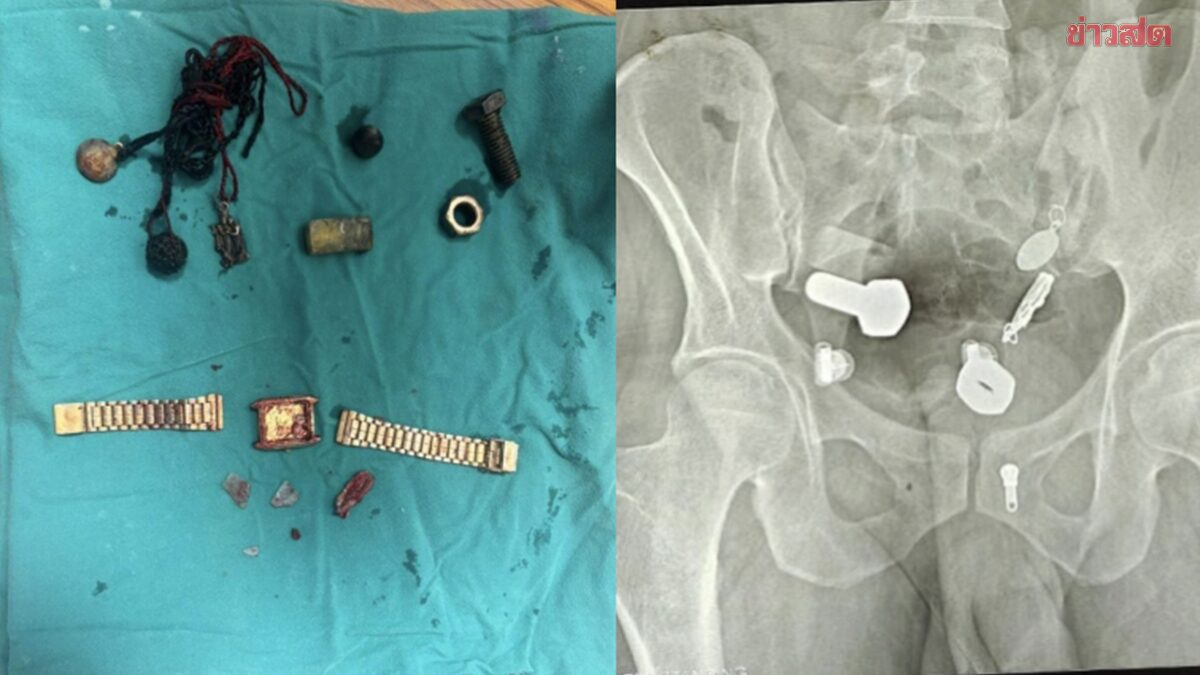

Các bác sĩ đã vô cùng kinh ngạc khi phát hiện một chiếc đồng hồ và vô số ốc vít trong bụng anh ta. Ca phẫu thuật kéo dài ba giờ.

Sau khi thăm khám và chụp X-quang, các bác sĩ thấy một chiếc đồng hồ đeo tay, bu lông và ốc vít, được gắn chặt vào nhau... trong bụng bệnh nhân.

Các bác sĩ đã cố gắng sử dụng ống nội soi để lấy vật thể ra nhưng không thành công, sau đó phải tiến hành một cuộc phẫu thuật lớn kéo dài hơn ba giờ để lấy toàn bộ dị vật ra khỏi cơ thể.

Theo Khaosod, đội ngũ y tế "sốc ngang" khi thấy nhiều vật thể, bao gồm cả một chiếc đồng hồ đeo tay trong bụng nam bệnh nhân. Sau phẫu thuật vài ngày tình hình sức khỏe bệnh nhân đang hồi phục tốt.